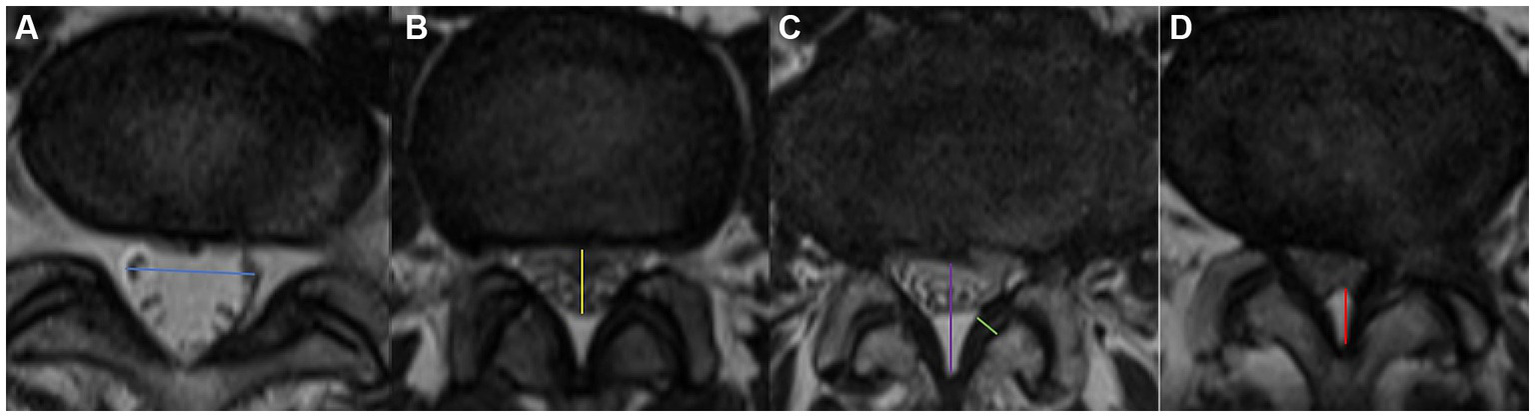

Measured at the intervertebral disc level by drawing a line between the left and right edges of the dural sac (Figure 2a).

Figure 2

Visualization of the measurement of blue arrow the TDD (a), yellow arrow the APDD (b), purple arrow the APDS (c), green arrow the LF thickness, and red arrow EF. Axial appearance of EF on T2-weighted MR images. The degree of fat accumulation at each intervertebral disc level was classified as follows: absent (a), concave (b), flat (c), or convex (d).

2.3.3 APDD

Measured at the intervertebral disc level by drawing a line between the anterior and posterior edges of the dural sac (Figure 2b).

2.3.4 APDS

Measured at the disc level by drawing a line between the posterior border of the disc and the LF at the midline (23) (Figure 2c). We divided LSS patients into three groups on the basis of the APDS value: abnormal: APDS between 12 mm and 15 mm; narrow: APDS between 10 mm to 12 mm; and extremely narrow: APDS less than 10 mm.

2.3.5 LF thickness

Measured at the midpoint of the mediolateral line of the LF perpendicular to its long axis (Figure 2c). LF hypertrophy (LFH) was defined as a thickness of 4.0 mm or greater on either side of the LF bilaterally, whereas nonthickening was defined as a thickness of less than 4.0 mm on both sides.